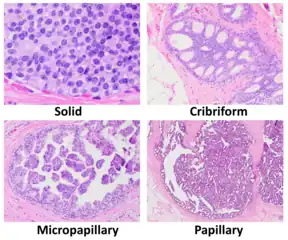

DCIS has been classified according to the architectural pattern of the cells (solid, cribriform, papillary, and micropapillary), tumor grade (high, intermediate, and low grade), the presence or absence of comedo histology,[8] or the cell type forming the lesion in the case of the apocrine cell-based in situ carcinoma, apocrine ductal carcinoma in situ.[9] DCIS can be detected on mammograms by examining tiny specks of calcium known as microcalcifications. Since suspicious groups of microcalcifications can appear even in the absence of DCIS, a biopsy may be necessary for diagnosis.

Histopathology of dystrophic microcalcifications in DCIS, H&E stain. Histopathologic architectural patterns of DCIS.[24]

Histopathologic architectural patterns of DCIS.[24]